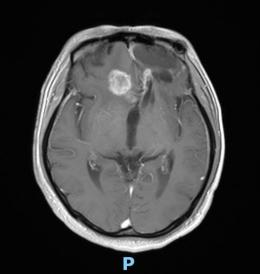

44歲的郭先生(化姓)為膠質(zhì)瘤復(fù)發(fā)患者,復(fù)查發(fā)現(xiàn)顱內(nèi)占位進(jìn)行性進(jìn)展1周,MRI檢查提示瘤體已累積到胼胝體,且瘤體位置較深,手術(shù)難度極高。面對這一挑戰(zhàn),王虎教授團(tuán)隊(duì)決定采用多種先進(jìn)技術(shù)輔助手術(shù),其中最為引人注目的就是首次引入的細(xì)胞級顯微鏡EndoSCell?。該設(shè)備是目前全球唯一實(shí)時(shí)在體細(xì)胞級顯影的儀器,可以輔助醫(yī)生從細(xì)胞層面區(qū)分腫瘤組織與正常組織,從而做到細(xì)胞級精準(zhǔn)切除。

患者術(shù)前核磁影像